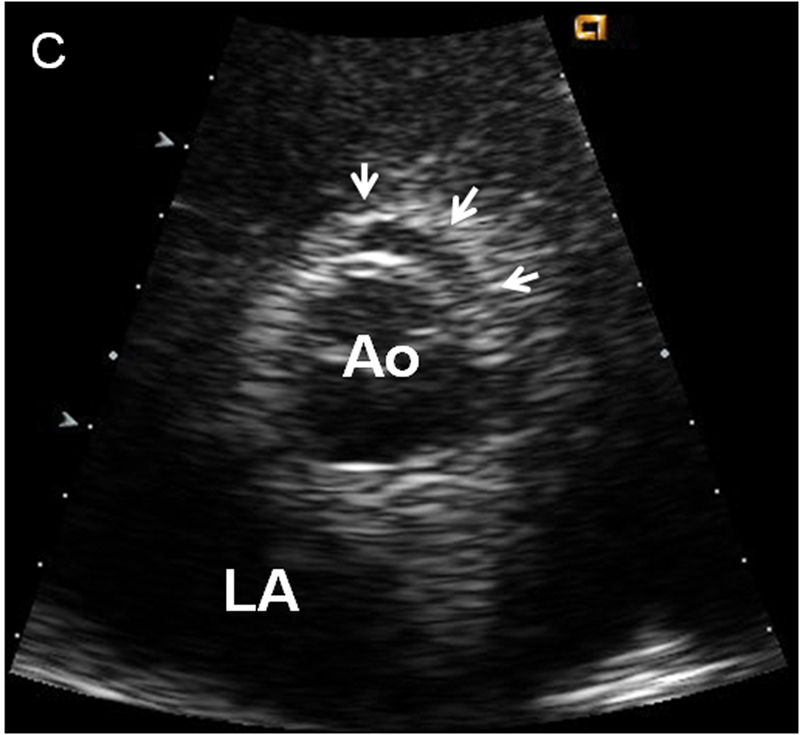

فحوصات تشخيصية لبعض امراض القلب والشرايين التاجية